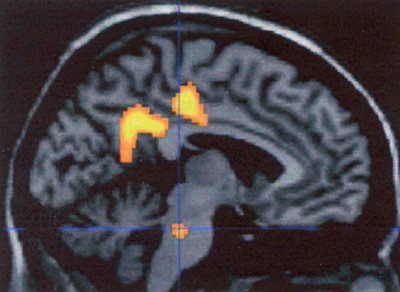

En «migrenegenerator» i hjernestammen ble postulert i 1995 da Weiler og medarbeidere med positronemisjonstomografi (PET) påviste aktivering i øvre del av hjernestammen under migreneanfall hos ni pasienter med migrene uten aura (37). Etter behandling med sumatriptan og smertefrihet i 30 minutter var dette senter i hjernestammen fortsatt aktivert, mens andre områder assosiert med smerte ikke var det. Senere studier har bekreftet disse funnene (fig 4), også hos to pasienter med migrene med aura (38). En studie viste forandringer i pons på samme side som smerten indusert av triglyserylnitrat, og bilateralt dersom pasienten fikk bilateral hodepine (39). Samlet er det sterke holdepunkter for at migrene innebærer en episodisk dysfunksjon i hjernestammen. Da migreneanfall sannsynligvis starter lenge før både aura og hodepine (40), gjenstår det å påvise aktivering i pons forut for migrenehodepinen. Hvorvidt den økte regionale blodgjennomstrømningen i hjernestammen er et resultat av aktivitet i nedstigende smerteinhiberende baner, er altså ikke avklart. Det er et problem å forklare sammenhengen mellom hjernestammedysfunksjon og kortikal hypereksitabilitet. Vi vet heller ikke hvordan triggerfaktorer får «begeret til å flyte over». Nøkkelen kan ligge i hypothalamus. Nylig klarte man med PET å påvise aktivering av hypothalamus under et spontant migreneanfall (41). At hypotalamisk aktivering ikke er blitt påvist i tidligere studier (37, 38), kan kanskje forklares med for dårlig bildeoppløsning (37) og at bildetakingen ble gjort opptil 24 timer etter hodepinedebut (38).